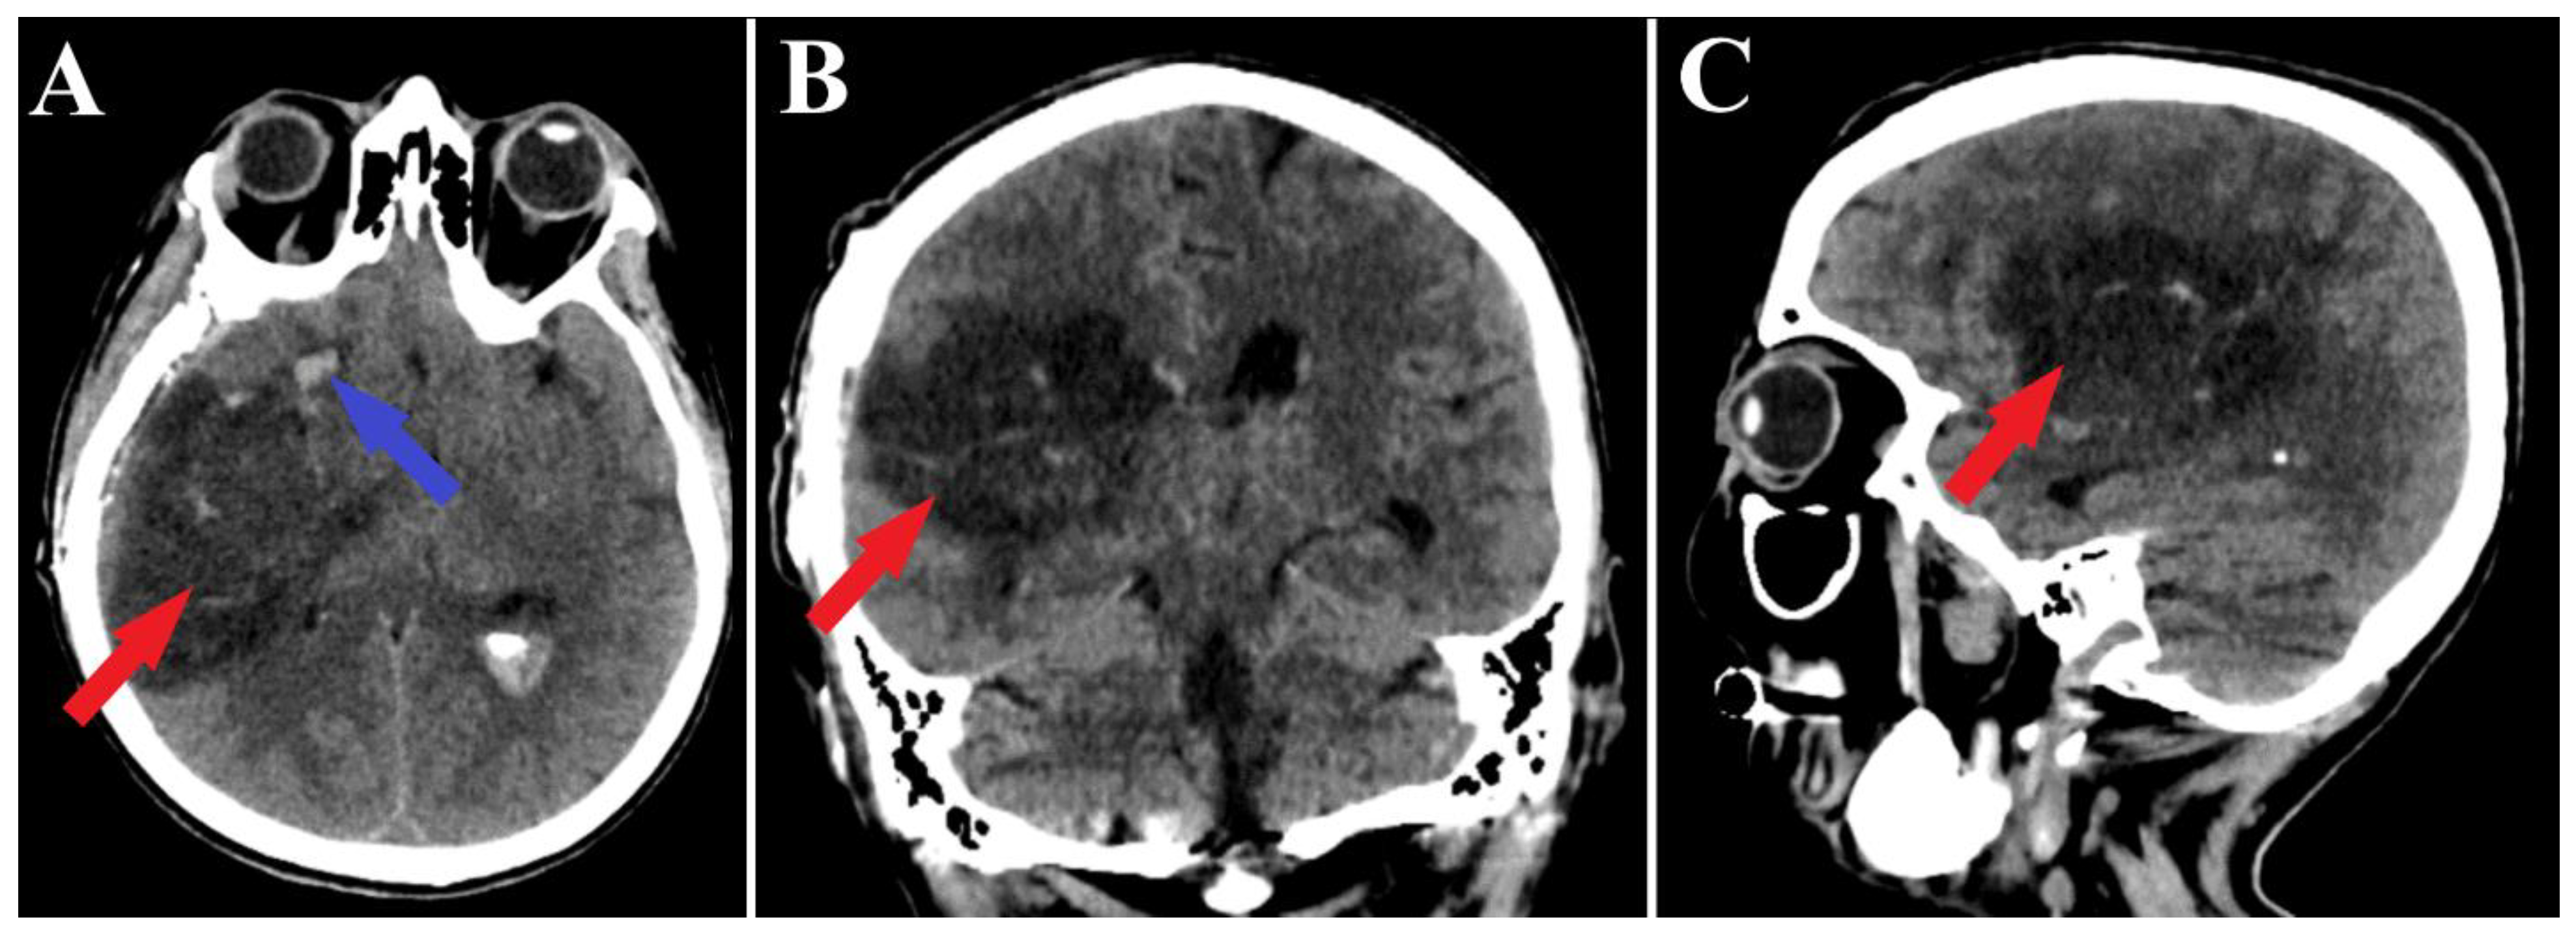

A follow-up non-contrast CT scan displayed a region of deep right fronto-temporal hypodensity, indicative of a post-surgical sequelae (Figure 4). Additionally, the CT scan identified areas of hemorrhage, which were deemed not to require further surgical intervention (Figure 5). Subsequent control angiography of the right carotid artery confirmed the complete excision of the AVM, with the preservation of the pathway of the right anterior choroidal artery (Figure 6). The patient was then managed with conservative treatment, resulting in a favorable clinical progression and substantial neurological improvement. After 2 weeks of hospitalization, at the time of discharge, the patient’s left hemiparesis had improved to 3/5 on the Medical Research Council (MRC) scale and assigned GCS was 12 points (eye response—3 points, verbal response—4 points, motor response—5 points).

Figure 4.

Postoperative CT scan, malformation resection shown. All three sections of the CT scan (A—axial section, B—frontal section, C—sagittal section) indicate a total resection of the arteriovenous malformation (red arrows), and the axial section of CT scan (A) depicts a small portion of an intraparenchymal hematoma (blue arrow).

Figure 5.

Postoperative CT scan, hematoma. Those images (A—axial section, B—frontal section, C—sagittal section) show a persistent pan ventricular and intraparenchymal hematoma (red arrow), as well as the contralateral intraventricular infiltration of the hematoma (blue arrows).